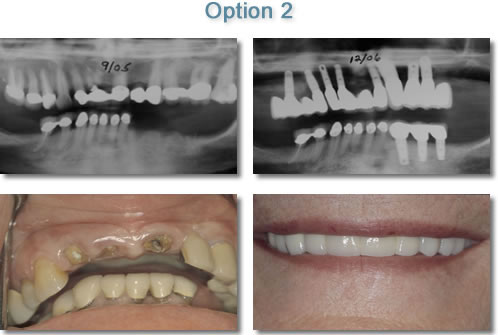

Porcelain to Metal Implant Supported Bridgework

Option 2: Porcelain to Metal Bridgework This option is like the bridges that your dentist has done routinely over the years to replace missing teeth but instead of teeth, Implants are used to support the bridgework. Porcelain to Metal Bridges on implants replacing a full arch of teeth may be the closest procedure to replicating a patient's original teeth. This procedure usually requires a minimum of 6 to 8 implants. In addition Bone Augmentation Procedures are often necessary.